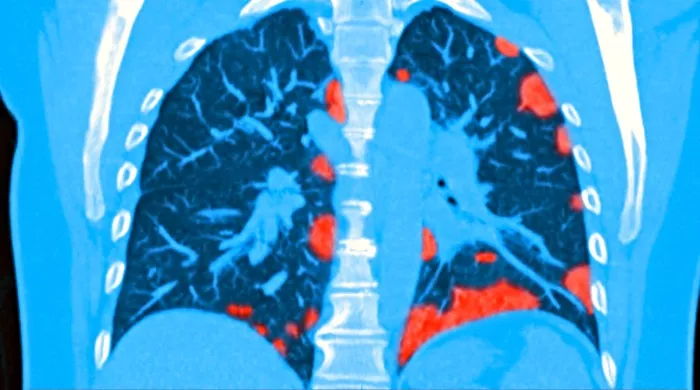

Doktorka Debora Li izdvojila je pet simptoma koji mogu da ukažu da je korona zahvatila vaša pluća. Ne treba ih ignorisati, jer je ova bolest izuzetno podmukla.

Iskustva iz Vuhana, odakle virus dolazi, pokazala su da je 81 odsto pacijenata primljeno sa blagim simptomima, dok se kod 14 odsto zaraženih razvila ozbiljna upala pluća, a oko pet procenata zahtevalo je intenzivnu negu.

Lekari prilikom procene da li su pluća ozbiljno ugrožena, pre svega zanima prelaz od blagog i umerenog do ozbiljnog i kritičnog stanja. Blago i umereno stanje može se lečiti kod kuće, dok ostali slučajevi traže bolničko lečenje.